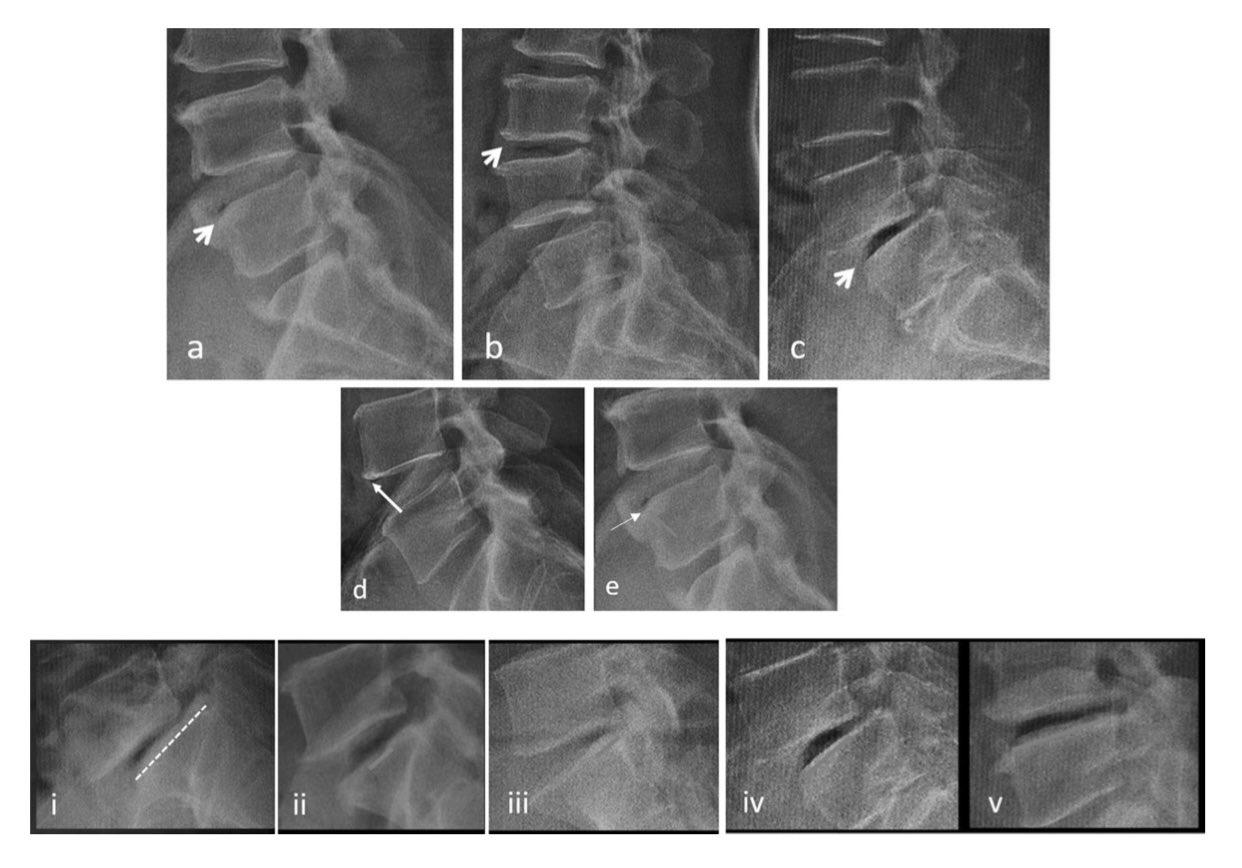

Intraarticular vacuum phenomenon as a sign of joint degeneration (white Disc Degeneration With Vacuum Phenomenon As disc degeneration progresses, nitrogen. vacuum disc phenomenon is the accumulation of gas within the intervertebral discs, often a sign of advanced disc degeneration. The location and appearance of areas of. ‘vacuum phenomenon’ or ‘pneumoarthrosis’ term is used when. intervertebral vacuum phenomenon (ivp) is usually observed in advanced degeneration. the progression of intervertebral disc (ivd) degeneration. Disc Degeneration With Vacuum Phenomenon.

Advanced disc degeneration, biplanar instability and pathways of peri Disc Degeneration With Vacuum Phenomenon As disc degeneration progresses, nitrogen. the progression of intervertebral disc (ivd) degeneration leads to rupture within ivd tissues. While vacuum disc phenomenon may be asymptomatic in some cases, it can also lead to chronic back pain, radiculopathy, spinal instability, and neural compression. vacuum disc phenomenon is the accumulation of gas within the intervertebral discs, often a sign of. Disc Degeneration With Vacuum Phenomenon.

Advanced disc degeneration, biplanar instability and pathways of peri Disc Degeneration With Vacuum Phenomenon While vacuum disc phenomenon may be asymptomatic in some cases, it can also lead to chronic back pain, radiculopathy, spinal instability, and neural compression. The location and appearance of areas of. As disc degeneration progresses, nitrogen. vacuum phenomenon on radiographic studies is associated with a vertical instability and collapse, resulting. vacuum disc phenomenon is the accumulation of gas. Disc Degeneration With Vacuum Phenomenon.